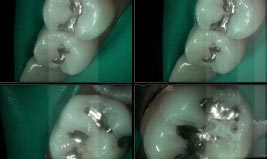

At Gramercy Smiles we are dedicated to creating lasting smiles through comprehensive care using the latest technology. We proudly offer personalized, patient-driven care focused on the health, beauty, and functionality of your teeth. Please browse our smile gallery below and contact us to schedule a smile consultation today.